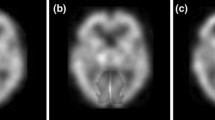

Iterative reconstruction techniques such as an ordered subsets-expectation maximization (OSEM) algorithm can easily incorporated various physical models of attenuation or scatter. We implemented OSEM reconstruction algorithm incorporating compensation for distance-dependent blurring due to the collimator in SPECT. The algorithm was examined by computer simulation to estimate the accuracy for brain perfusion study.Methods: The detector response was assumed to be a two-dimensional Gauss function and the width of the function varied linearly with the source-to-detector distance. The attenuation compensation (AC) was also included. To investigate the properties of the algorithm, we performed computer simulations with the point source and digital brain phantoms. In the point source phantom, the uniformity of FWHM for the radial, tangential and longitudinal directions was evaluated on the reconstruction image. As for the brain phantom, quantitative accuracy was estimated by comparing the reconstructed images with the true image by the mean square error (MSE) and the ratio of gray and white matter counts (G/W). Both noise free and noisy simulations were examined.Results: In the point source simulation, FWHM in radial, tangential and longitudinal directions were 14.7, 14.7 and 15.0 mm at the image center and were 15.9, 9.83 and 10.6 mm at a distance of 15 cm from the center by using FBP, respectively. On the other hand, they were 8.12, 8.12 and 7.83 mm at the image center, and were 7.45, 7.44 and 7.01mm at 15 cm from the center by OSEM with distance-dependent resolution compensation (DRC). An isotropic and stationary resolution was obtained at any location by OSEM with DRC. The spatial resolution was also improved about 6.5 mm by OSEM with DRC at the image center. In the brain phantom simulation, the blurring at the edge of the brain structure was eliminated by using OSEM with both DRC and AC. The G/W was 2.95 and 2.68 for noise free and noisy cases, respectively, when no compensation was performed. But the values for G/W without and with noise became 3.45 and 3.21 with AC only and were improved to 3.75 and 3.71 with both AC and DRC. The G/W approached the true value (4.00) by using OSEM with both AC and DRC even when there was statistical noise.Conclusion: In conclusion, OSEM reconstruction including the distance-dependent resolution compensation algorithm was reasonably successful in achieving isotropic and stationary resolution and improving the quantitative accuracy for brain perfusion SPECT.